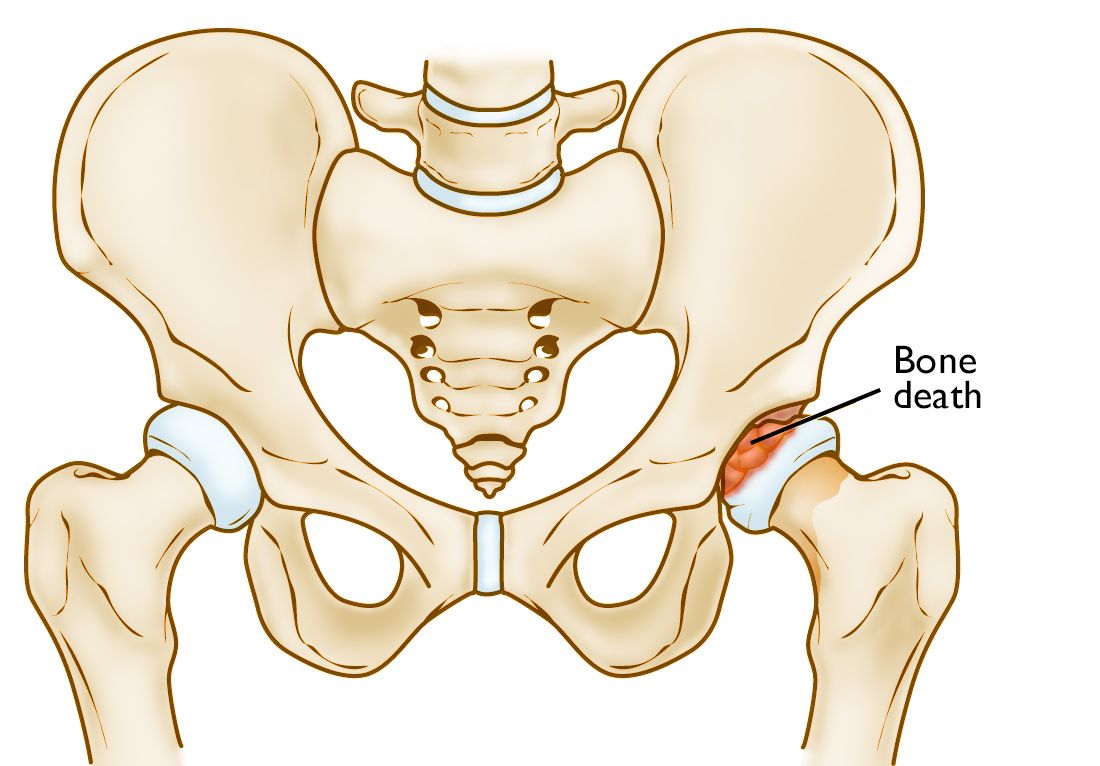

From www.sciencephoto.com

LeggCalvePerthes disease, illustration Stock Image F037/6850 Legg Calve Disease It can cause hip pain, stiffness, and limp, and may. Learn about the diagnosis and treatment of perthes disease, a condition that affects the hip joint in children. It occurs when the blood supply to the head of the femur (thighbone) is disrupted. Without an adequate blood supply, the bone cells die, a process called avascular necrosis. It occurs when. Legg Calve Disease.